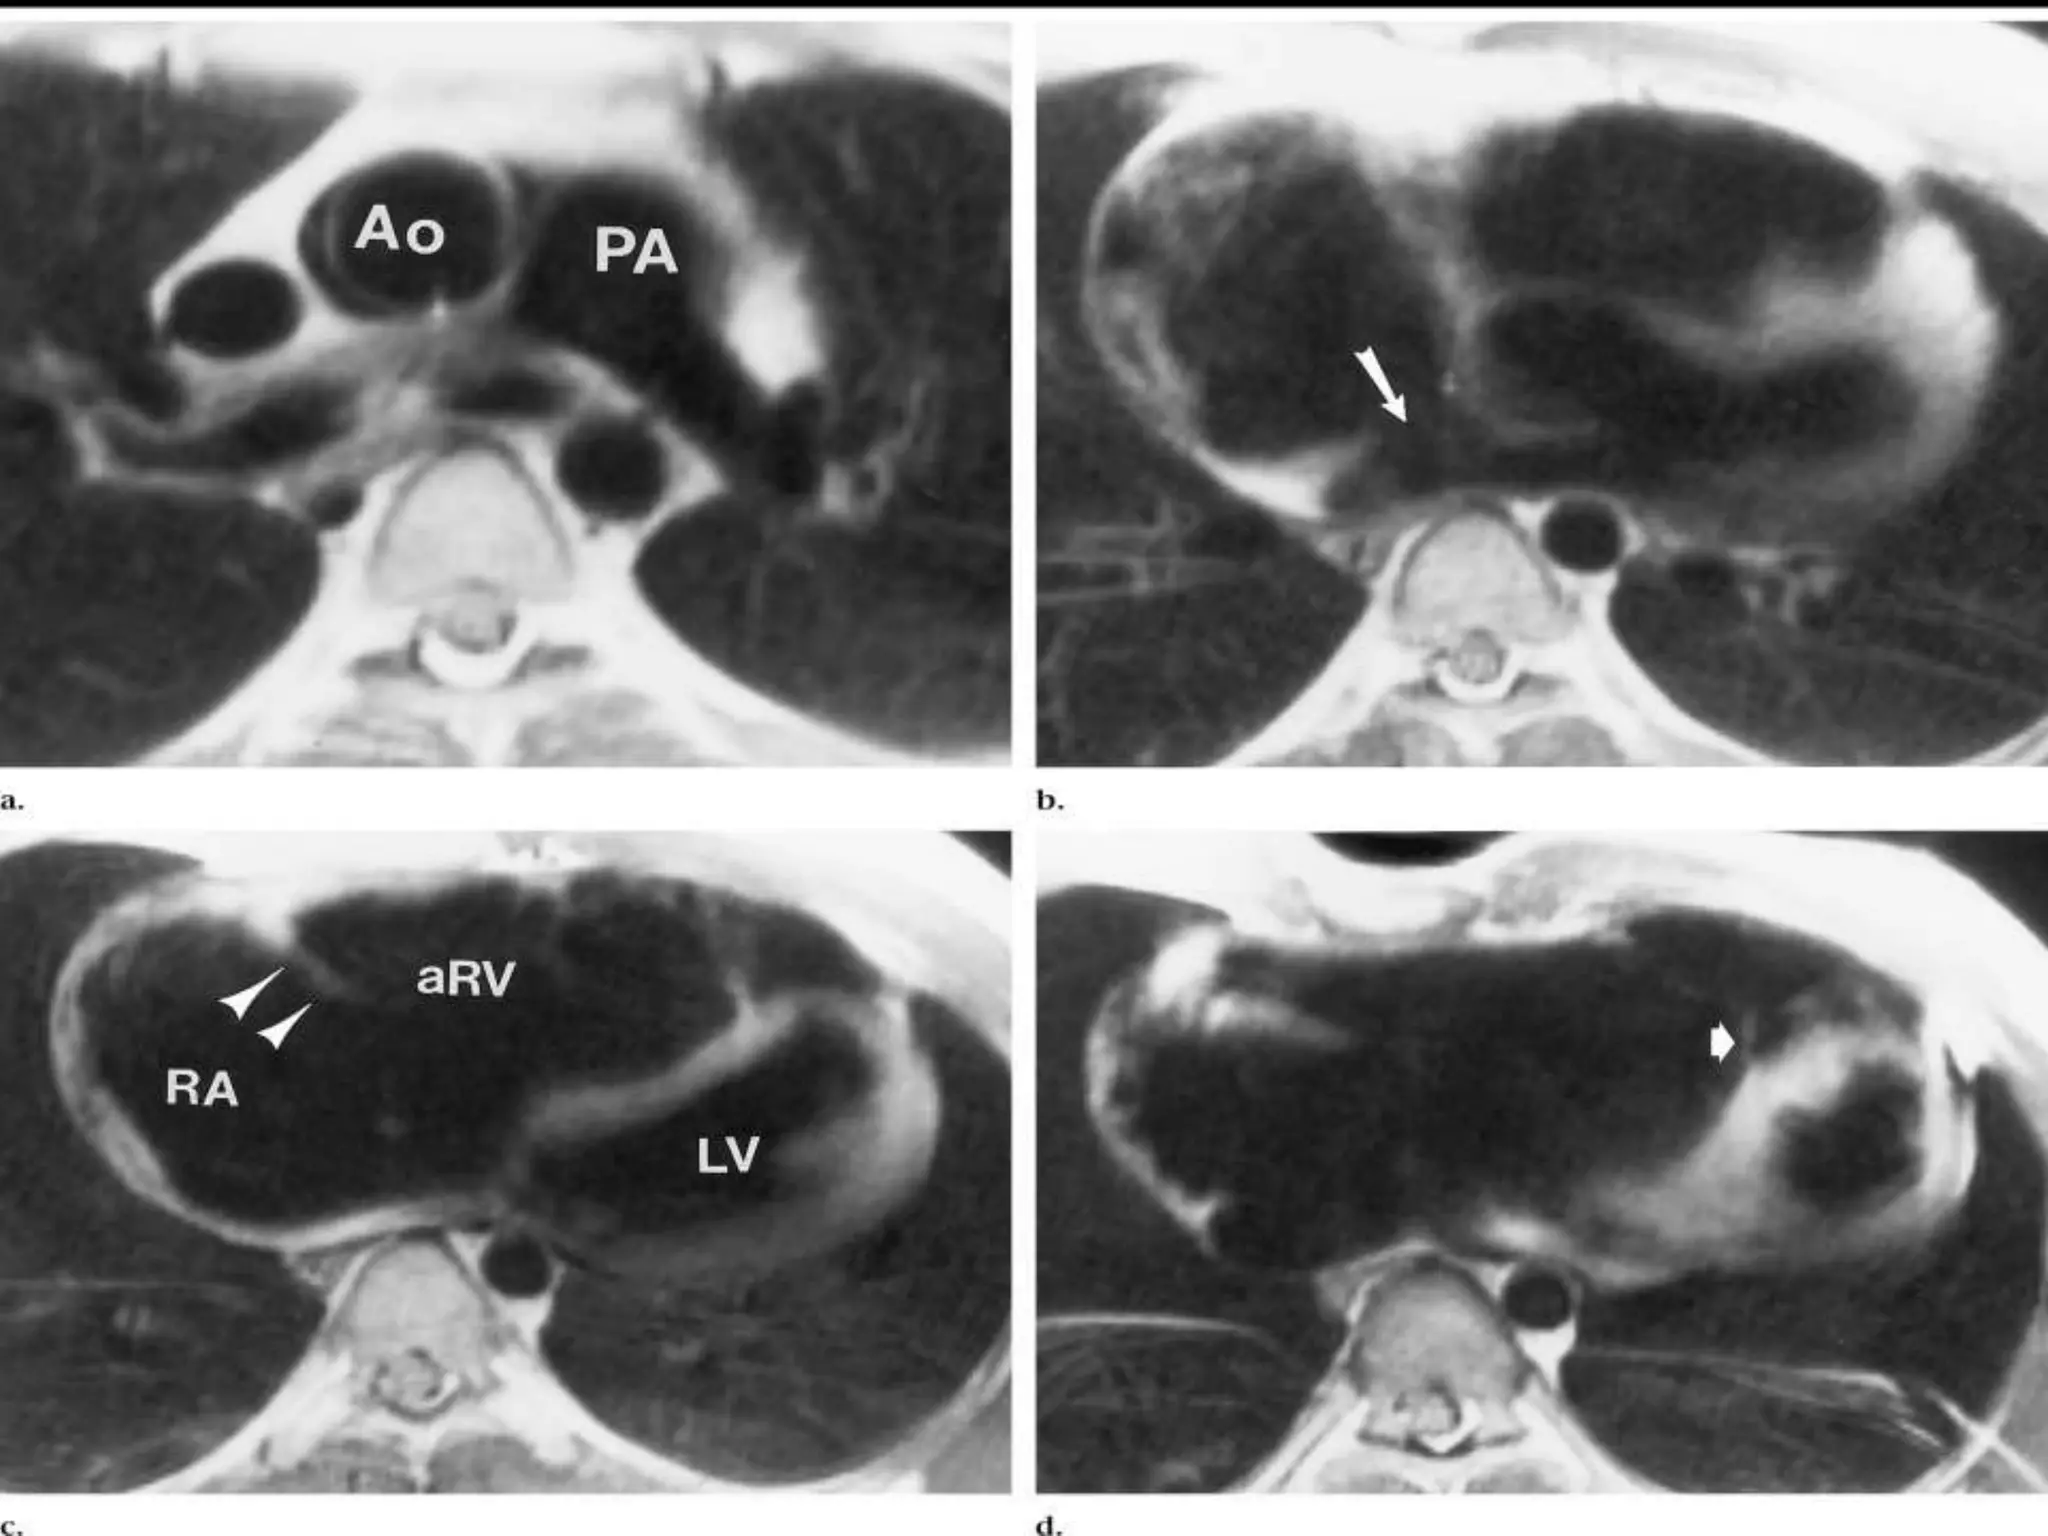

Cardiac MRI

 CMR imaging has emerged as another tool for

evaluation of Ebstein’s patients

 It provides quantitative measurement of right

atrial and ventricular size and systolic function

even in the presence of significant distortion of

right ventricular anatomy.